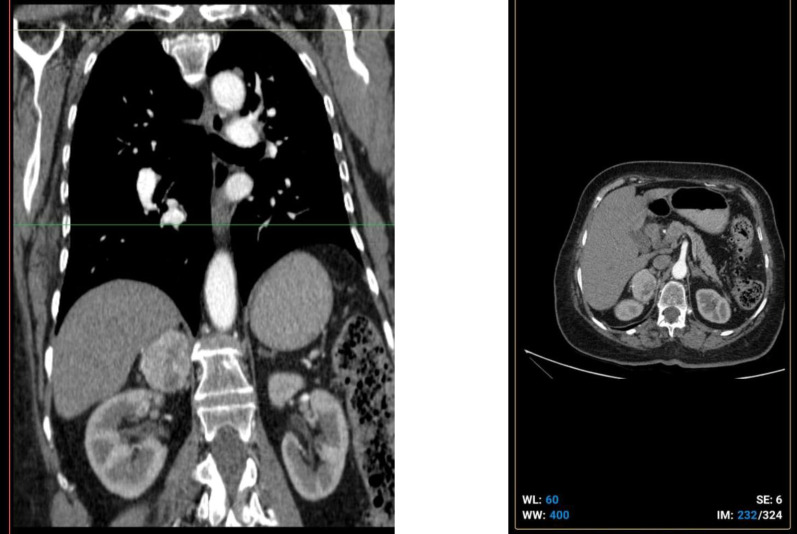

Case presentation: A 71-year-old woman with a history of breast carcinoma-status post mastectomy 7 years prior-presented with elevated levels of cancer antigen 15-3 (CA15-3), raising suspicion of disease recurrence or metastasis. Imaging studies revealed a mass in the adrenal gland. Surgical excision of the adrenal lesion was performed, and subsequent histopathological and immunohistochemical analyses confirmed the coexistence of two distinct tumor components: primary pheochromocytoma and metastatic breast carcinoma.